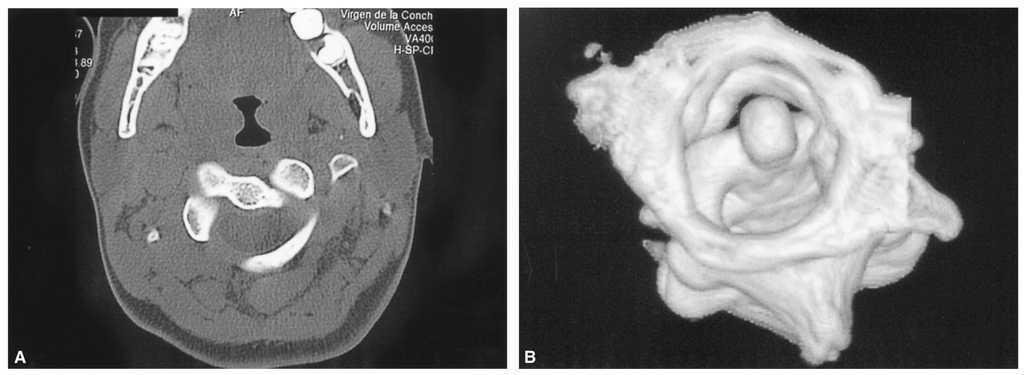

Paciente varón de 9 años con tortícolis asociada a fractura de clavícula por una caída en gimnasia. Tratado en su ciudad de origen mediante vendaje en 8 para la fractura de clavícula, y relajantes musculares y fisioterapia, fue remitido a nuestro centro a las 15 semanas por persistencia de la sintomatología (fig. 1). Las radiografías eran poco demostrativas, por lo que se practicaron estudios mediante TAC y RMN diagnosticándose de SRCAA tipo I3, con una divergencia C1-C2 de 42° (fig. 2); se instauró tracción halo-gravedad progresiva hasta un peso de 7 kg, en que se detuvo por aparición de disartria (17 días de tracción), con una movilidad rotacional levemente disminuida, la TAC de control mostró una divergencia residual de 11°, por lo que para evitar la recidiva se efectuó un artrodesis posterior C1-C2 in situ con injerto de cresta ilíaca (fig. 3), manteniendo la tracción durante la intervención e inmovilizándose con halo-yeso 3 meses. Una vez retirada la tracción, la disartria remitió espontáneamente. Quince años después, el paciente presenta una movilidad cervical prácticamente normal, con una limitación de la rotación izquierda de 10°.

Figura 2. Imagen de la tomografía axial computarizada (TAC) del paciente n.O 1 que muestra el método de medición, con una divergencia atlanto-axial de 42°.

Niño de 7 años de edad con historia de tortícolis fija de 17 semanas de evolución a raíz de una infección respiratoria superior; antes de ser remitido, fue tratado mediante antiinflamatorios no esteroideos (AINE), ortesis cervical tipo Schanz y tracción elástica seguida de ortesis cervical sin resultado positivo. Mediante TAC se diagnosticó de SRCAA ipo I con una divergencia de 25° (fig. 4) y se inició un tratamiento con tracción hasta llegar a 8 kg, a las 3 semanas presentó unas rotaciones simétricas y la TAC (fig. 5) mostró una reducción completa, por lo que se inmovilizó mediante halo-yeso que se mantuvo 6 semanas, continuándose el tratamiento 6 semanas más con ortesis cervical blanda. Ocho años después, la función es normal, no presentando secuelas.

Figura 4. Tomografía axial computarizada donde se puede apreciar la deformidad rotacional del complejo C1-C2 en el segundo paciente con angulación de 25°.

Mujer de 16 años con historia por tortícolis fija aparecida tras cirugía tiroidea; tratada mediante AINE y ortesis cervical blanda, no mejora por lo que a las 10 semanas es enviada a nuestro centro. El diagnóstico, SRCAA tipo I de Fielding, se obtuvo mediante TAC (fig. 6A) con reconstrucción tridimensional (fig. 6B) utilizándose el mismo protocolo de tratamiento que en los otros pacientes, llegando a 14 kg; a las 3 semanas la movilidad era simétrica y la TAC confirmó la reducción completa de la divergencia rotacional (fig. 7), inmovilizándose con halo-yeso 6 semanas y ortesis cervical blanda otras 6 semanas. Dos años después, la función es completamente normal, no habiendo presentado episodios de cervicalgia ni tortícolis.

Figura 6. A: tomografía axial computarizada convencional en la que se puede apreciar la rotación de 32° entre C1-C2 en el paciente n.O 3. B: la reconstrucción tridimensional nos muestra la deformidad típica de rotación y pinzamiento C1-C2.

El diagnóstico radiológico es difícil, ya que la deformidad y el dolor impiden obtener buenas proyecciones, así en la radiografía anteroposterior simple se superpone la cabeza, y en la lateral se puede observar una falta de paralelismo entre el cráneo y la columna; la radiografía transoral de odontoides puede ser de gran valor, mostrando una asimetría entre el diente del axis y las masas laterales del atlas con posible pinzamiento de las facetas8. Se ha sugerido la utilización de la TAC dinámica, con rotación a izquierda y derecha de la cabeza, pero en situación de SRCAA la movilización es dolorosa, por lo que difícilmente se obtendrá la cooperación del paciente, pudiendo llevar a confusión en el diagnóstico13. En una tortícolis aguda no parece estar indicado el estudio con TAC14,15, pero en casos persistentes con sospecha de SRCAA es muy útil para confirmar el diagnóstico, ya que mostrará la divergencia rotacional C1-C2 que se puede cuantificar midiendo la angulación existente entre las líneas que unen las apófisis transversas del atlas y del axis (fig. 2)16. En la TAC tridimensional se puede apreciar la deformidad rotacional con el desplazamiento completo de las facetas articulares, la situación asimétrica de la odontoides en el arco anterior del atlas --que asimismo puede orientar sobre la integridad del ligamento transverso-- y el desplazamiento de la espinosa de C24. La RMN es un buen complemento, ya que puede informar de interposición de partes blandas7, así como de la posible lesión del ligamento transverso17, por lo que en caso de duda puede indicar la necesidad de estabilización quirúrgica. En nuestra serie, ante una sospecha de SRCAA, se utilizó la TAC simple como método diagnóstico (fig. 2 y 4A), completándose en el tercer caso con reconstrucción tridimensional (fig. 4B) en la cual fueron muy evidentes las alteraciones torsionales del complejo atlantoaxial.